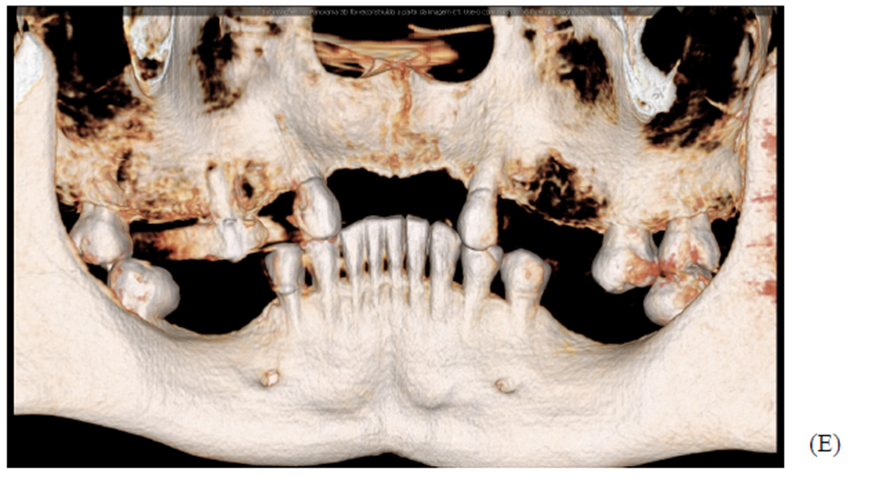

Figuras A,B,C, D e E: imagens evidenciando grande perda óssea anterior no sentido horizontal, bem como a vestibularização do rebordo anterior, o que impossibilita a instalação dos implantes em um bom posicionamento tridimensional.